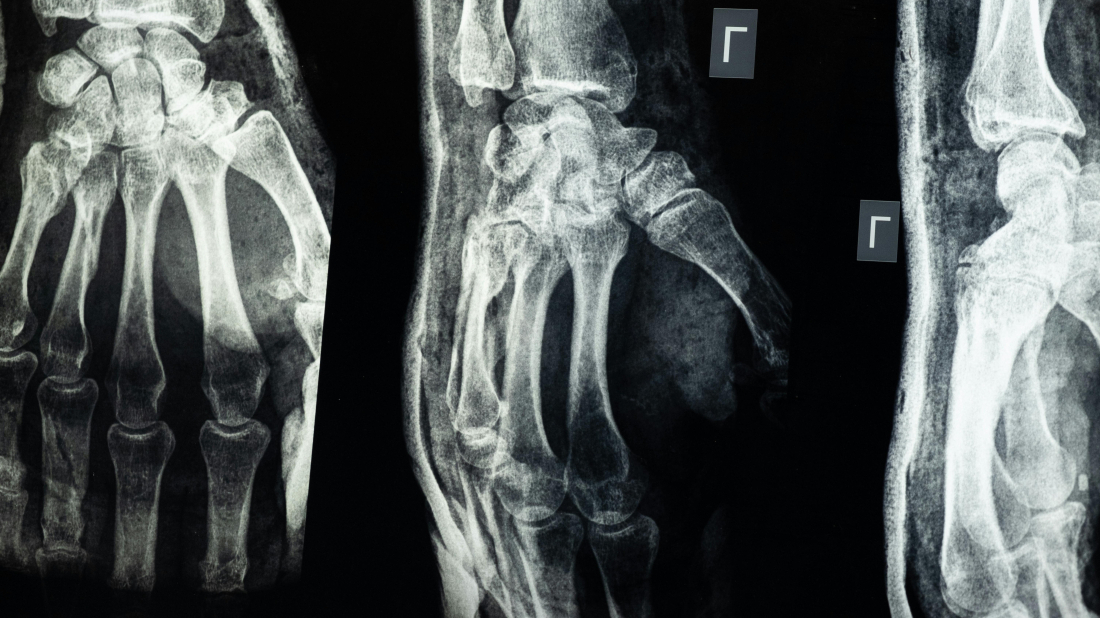

Osteoporoza je progresivna metabolička bolest kostiju koju karakterizira smanjenje gustoće i propadanje strukture koštanog tkiva. Kosti postaju porozne i slabe, što dramatično povećava rizik od prijeloma čak i pri najmanjem naporu ili padu.

Ono što osteoporozu čini posebno podmuklom jest činjenica da se razvija godinama, bez očitih simptoma. Često se dijagnosticira tek nakon prvog prijeloma, kada je bolest već uznapredovala.

Najčešći su prijelomi kuka, kralježnice i ručnog zgloba, koji mogu dovesti do kronične boli, dugotrajne nesposobnosti, gubitka neovisnosti, pa čak i preuranjene smrti.

Procjenjuje se da će 1 od 3 žene i 1 od 5 muškaraca starijih od 50 godina doživjeti osteoporotski prijelom. Unatoč tome što postoje učinkovite metode dijagnostike i liječenja, šokantan je podatak da čak do 80 % pacijenata koji su doživjeli prijelom zbog krhkosti kostiju nema odgovarajuću dijagnozu niti liječenje za temeljnu bolest – osteoporozu.